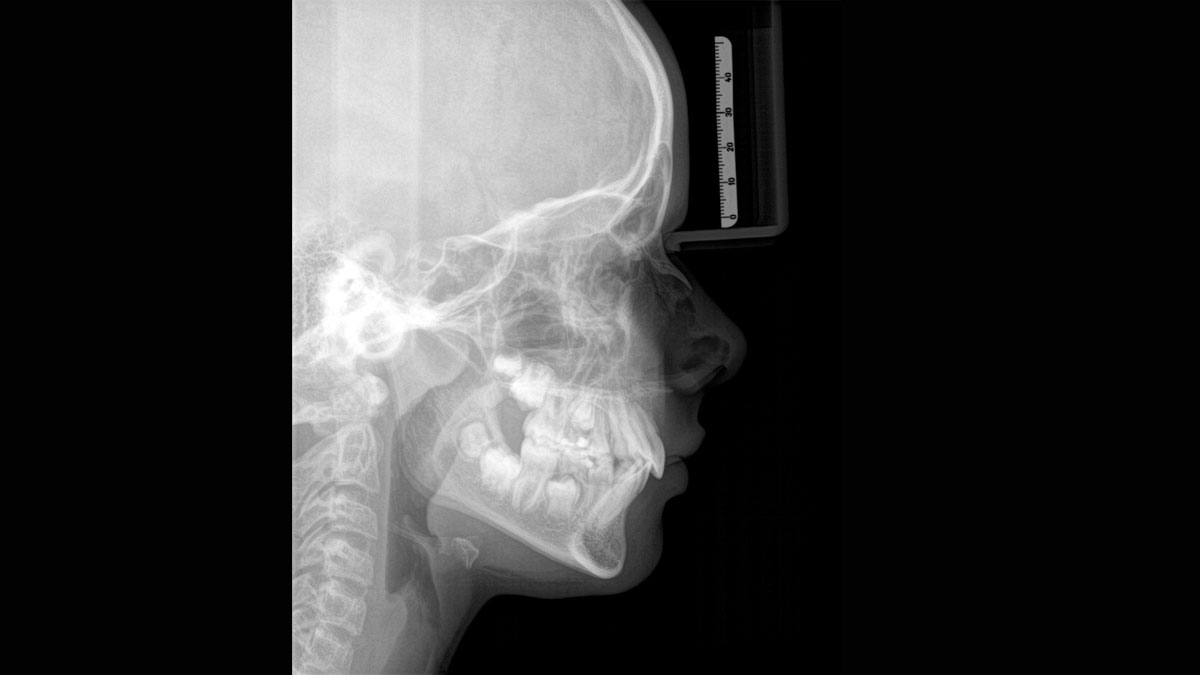

При помощи такого оборудования специалист сможет успешно решить широкий спектр диагностических и лечебных задач. Качественное изображение, достоверность при разноуровневой резкости (технология Sharp Layer), гибкий объём, 30 доступных вариантов цвета. Цефалометрическая визуализация позволяет получать боковые или симметричные снимки, а также определить положение при смещении зуба. Работая при разрешении до 80 мкм в режиме низкой дозы и HD, вы получаете качественные изображения выбранного формата, заботясь о комфорте и безопасности пациента.

Диагностика последнего поколения, идеально решающая задачи рентгеновского обследования независимо от размеров клиники. Поля изображения зависят от определенной клинической картины, поэтому специалистам так удобно работать с ORTHOPHOS SL 3D. Данная установка делает объёмные картинки для одиночной реставрации в 3D качестве полностью всей челюсти такого размера, которого требуется.

Планирование одиночной реставрации, эндодонтические исследования и пр. – для этого специалист может выбрать объёмные варианты 8 х 8 см или 11 х 10 см, также предлагается объём 5 х 5,5 см. Снимки в HD-качестве, стандартные настройки или выбор объёма обследования в зависимости от диагноза — всё это врач получает в отличном качестве, а для пациента излучение в районе исследования минимально.